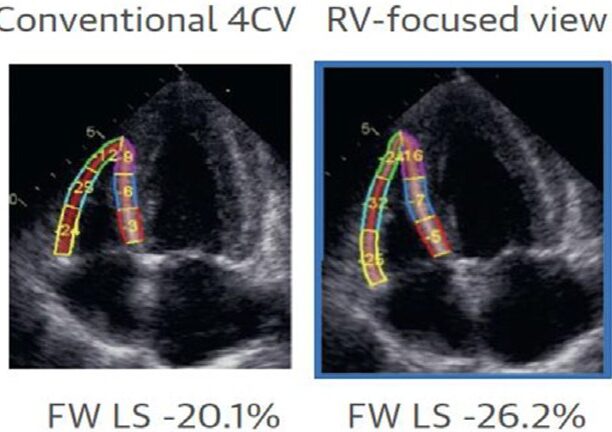

(8) Utilizar a janela apical 4C padrão para avaliação do ventrículo direito pode subestimar os valores do strain de parede livre, sobretudo nos segmentos mais distantes do septo interventricular.

Quanto ao strain longitudinal do ventrículo direito (parede livre), um valor de normalidade entre -26.4 ± 4.2%, com limite inferior de normalidade considerado -18.2% foi proposto previamente em análise com > 1.000 indivíduos saudáveis.

- O limite inferior de normalidade do strain de parede livre do VD deve ser de 20% em homens e de 21% em mulheres, com valores inferiores devendo ser considerados patológicos;